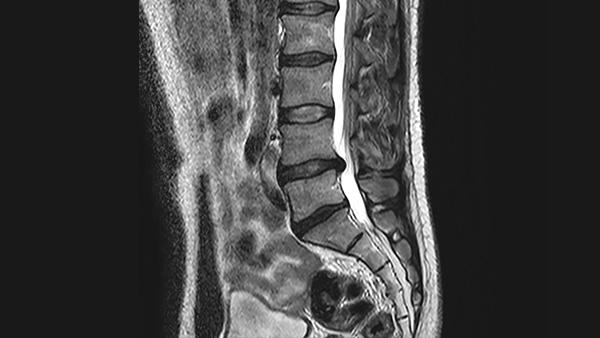

MRI of the spine showing one herniated disc that is pressing on the spinal cord

Defining the Molecular Origin of Back Pain

Orthopedic and biomedical engineering faculty at Columbia demonstrate, for the first time, that severity of disc herniation is associated with changes in circulating levels of inflammatory cytokines. They also identified three novel molecular mediators of increasing severity in patients with chronic back pain with the potential to guide the development of individually tailored treatment approaches. To better understand the influence of inflammation on intervertebral disc cell mechanics, the research team undertook a study of the relationship between serum cytokine profiles and structural indicators of spine disease with a goal to identify biochemical markers that could determine the molecular origin of pain. Their findings, published in the October 2020 issue of Osteoarthritis and Cartilage, provide evidence that cytokine levels are elevated in the serum of patients with disc herniation and that the patient-specific covariates of age, BMI, and gender are significant contributors to some cytokines.

Severity of disc herniation is associated with changes in circulating levels of inflammatory cytokines.